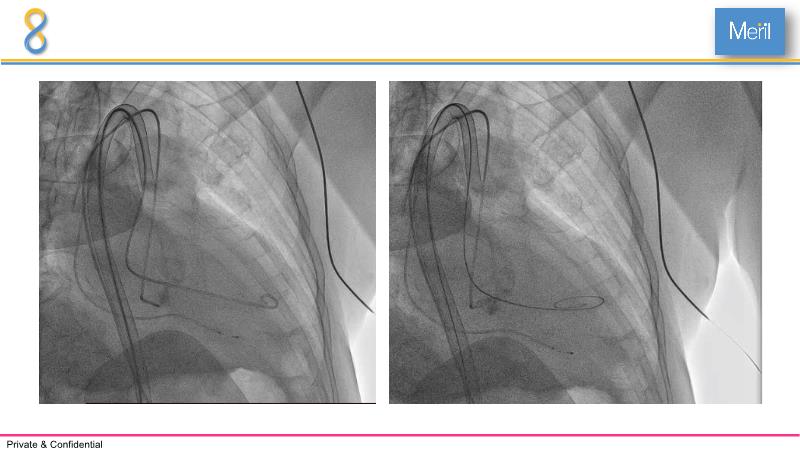

Through the presentation of several compelling cases, including an 88-year-old male with CKD, RBBB, moderate LV dysfunction, and severe aortic stenosis, a Type 1a bicuspid native AS, and an extraordinary TAVI in an 83-year-old with acute heart failure and comorbidities, this session will dive into the Myval Octapro THV. Learn about its key features, procedural impact, and potential clinical benefits. Discover the Octalign technique for predictable and precise commissural and coronary alignment, preserving coronary access. Gain insights into precise sizing, positioning, and deployment of the Myval THV series in real-world scenarios, and explore the relevance of pivotal Landmark RCTs in clinical practice.

- To know the Octalign technique which enables predictable and precise commissural and coronary alignment thus preserving coronary access

- To understand the technique of precise sizing, positioning and deployment of Myval THV series in real world clinical scenarios